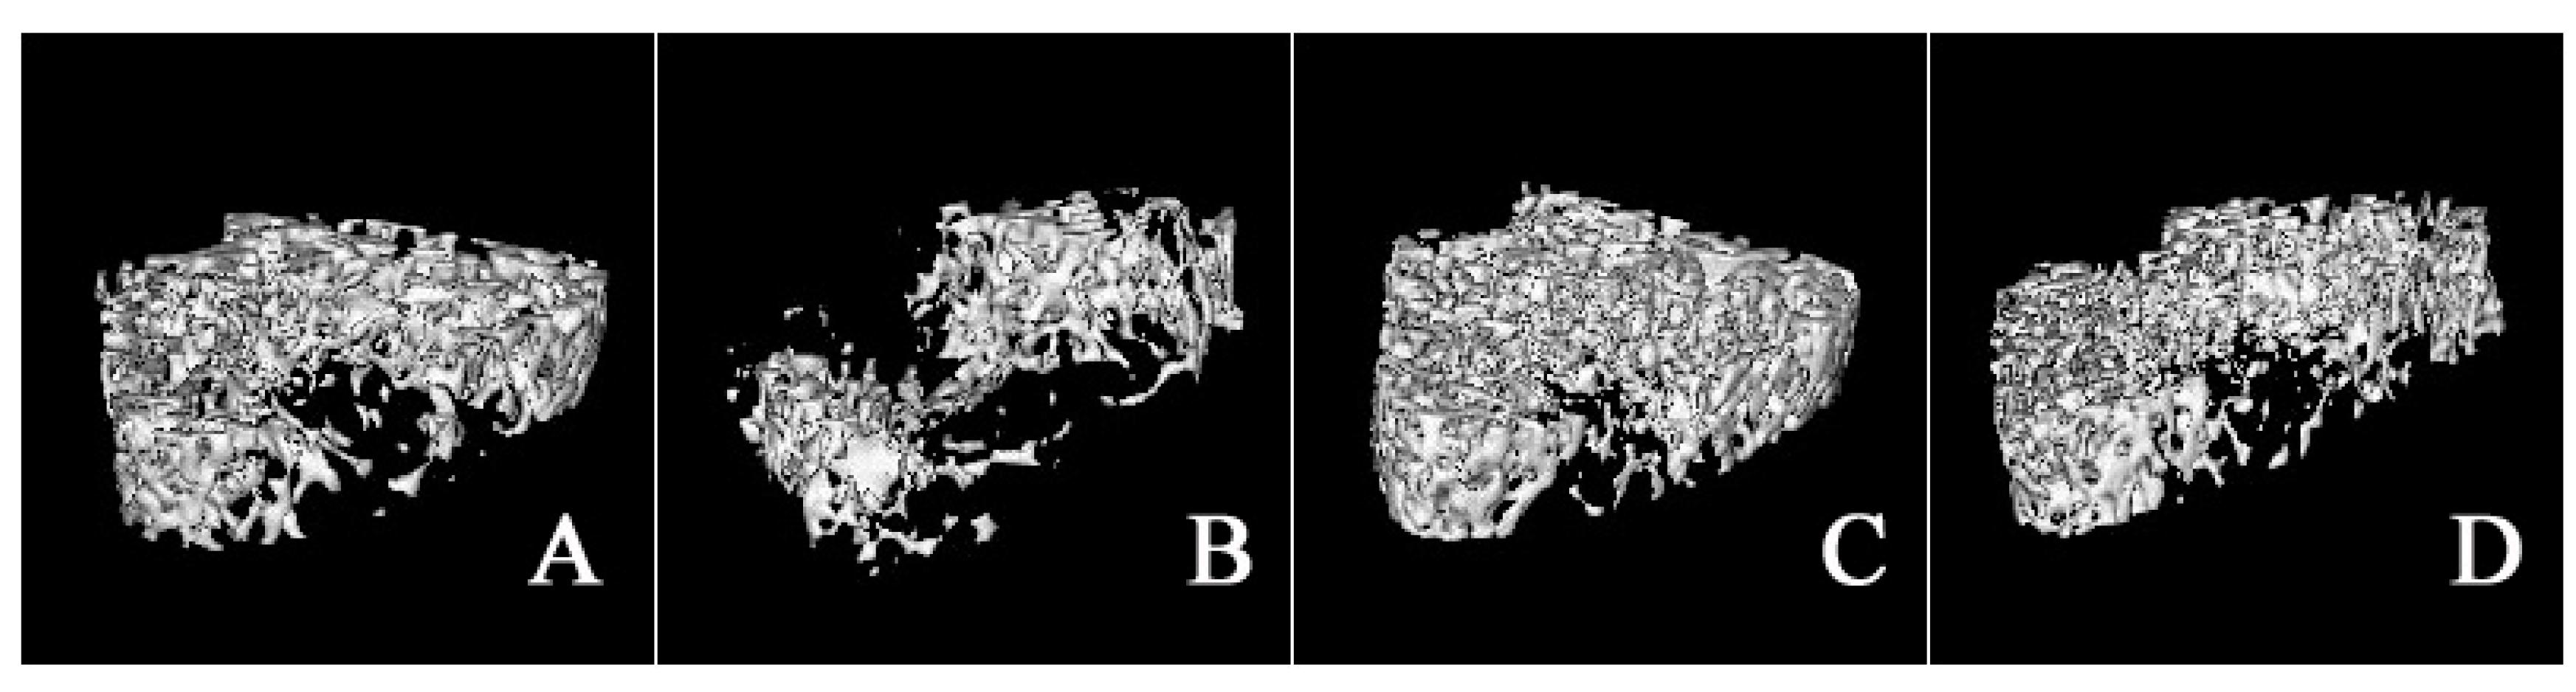

2.3. Micro-Architecture of Femoral Trabecula